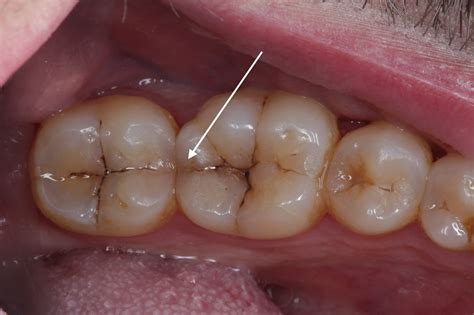

Discovering a crack in tooth can be a source of immediate anxiety, often accompanied by sharp pain, sensitivity, or a feeling that something just isn't right when you bite down. Whether it happened while eating a hard piece of candy, grinding your teeth at night, or simply due to natural wear and tear over the years, a dental fracture is a serious issue that requires professional attention. Ignoring these cracks—even if they seem minor—can lead to severe complications, including infection, abscesses, or even the eventual loss of the tooth itself. Understanding the different types of cracks, recognizing the symptoms, and knowing when to see a dentist is essential for preserving your oral health.

A crack in tooth does not always cause pain, which makes it tricky to identify. Sometimes the crack is so small (a craze line) that it is only visible to a dentist. Other times, the symptoms are unmistakable. Watch for the following warning signs:

Not all cracks are created equal. Dentists categorize them based on severity and location. Here is a breakdown to help you understand the potential implications of a crack in tooth:

Craze Lines Tiny cracks only in the outer enamel. Generally harmless. Usually no treatment needed; cosmetic only.

Fractured Cusp A piece of the tooth's chewing surface breaks off. Often requires a crown to restore the shape.

Cracked Tooth A crack runs from the chewing surface down toward the root. Usually needs a crown to prevent the crack from spreading.